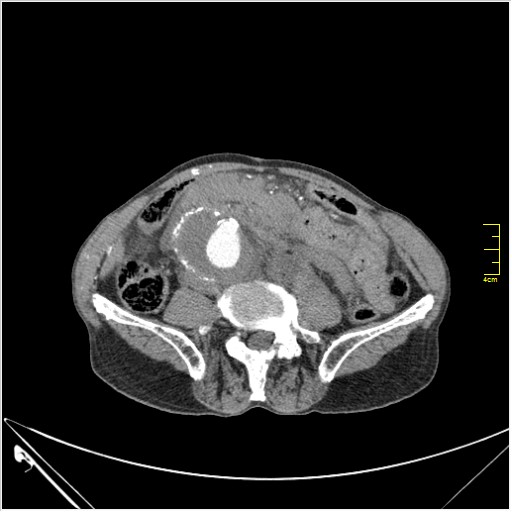

КТ брюшной полости. Мужчина с пальпируемой опухолью в животе

Пациент Т. 64 года, обратился на КТ брюшной полости амбулаторно (!), по направлению семейного врача с диагнозом abdominal mass, буквально: образование брюшной полости.